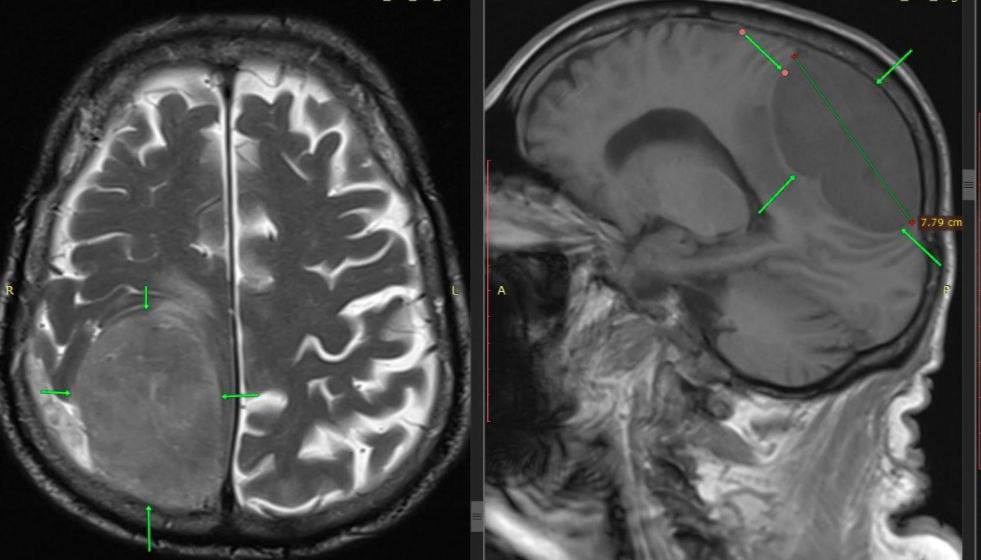

Опухоль размером с лимон удалили нейрохирурги в Пятигорске у 85-летнего пациента.

Мужчину доставили с симптомами инсульта: не двигалась левая половина тела. Но обследование показало другое — гигантское новообразование в зоне мозга, отвечающей за движение.

Нейрохирурги провели сложнейшую операцию и полностью удалили опухоль. Несмотря на высокий риск и возраст пациента, вмешательство прошло успешно.

Фото: ГКБ Пятигорска.